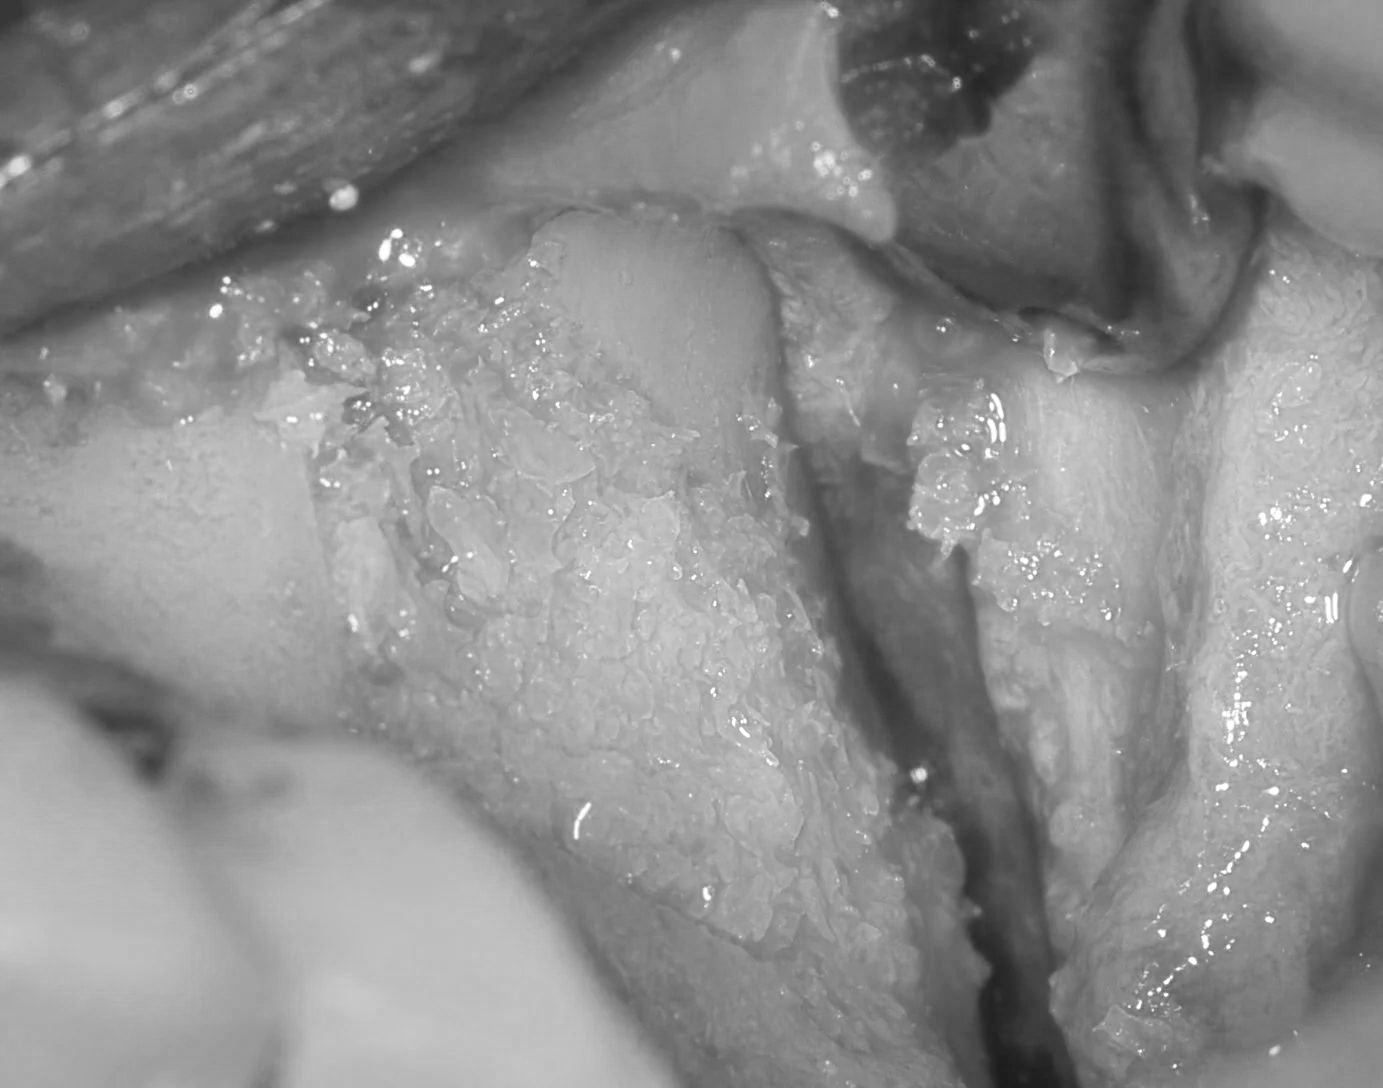

4. Bone Grafting

The newly created sinus cavity and the surrounding implant sites were filled with a mixture of particulate allograft and xenograft materials. This ensured stable bone regeneration around the implant surfaces and under the elevated sinus membrane. A resorbable collagen membrane was positioned over the lateral window to protect the graft and support guided bone regeneration. The site was then sutured for tension-free primary closure.